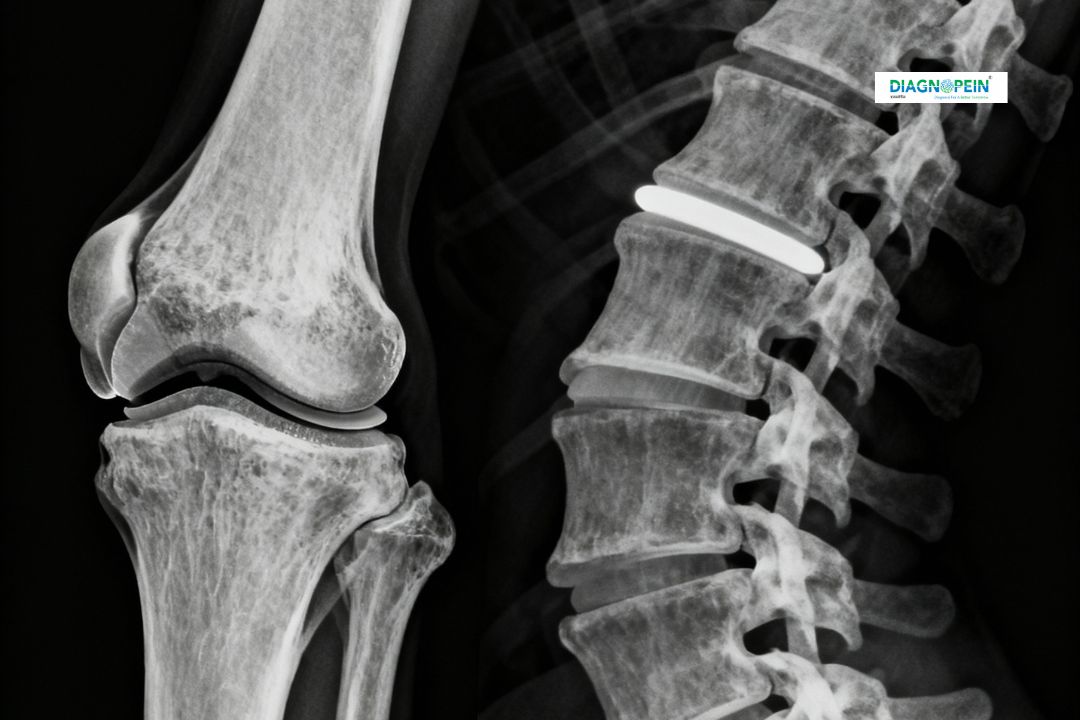

At Diagnopein Karad, the X-Ray Knee Joint (Spine) test is a vital diagnostic imaging service that helps in assessing bone structure, alignment, and potential degenerative or traumatic conditions. This imaging modality uses low-dose radiation to produce clear images of your knee or spinal bones, assisting doctors in evaluating fractures, arthritis, dislocations, or post-surgical progress.

An X-Ray Knee Joint (Spine) test plays an essential role in identifying skeletal abnormalities and monitoring joint or spinal health. It helps radiologists and orthopedic specialists determine the severity of conditions and design a precise treatment plan.

The X-Ray Knee Joint (Spine) evaluates several structural parameters such as:

1. Bone density and joint spacing

2. Alignment of the knee or spinal bones

3. Signs of wear, deformation, or degeneration

4. Presence of bone spurs or fracture lines

5. Post-surgical fixation device positioning

These parameters help in assessing injury severity, degenerative changes, and alignment corrections. Accurate readings allow specialists to plan better treatments for orthopedic and spinal conditions.